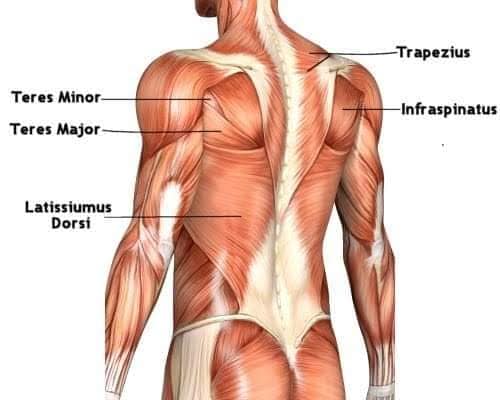

Спинні м'язи

Спинні м'язи виконують функції підтримки хребта, а також дозволяють здійснювати рухи тулуба.

Поверхневі спинні м'язи

М'язи, що піднімають лопатку: Трапецієподібний м'яз: великий м'яз, що покриває верхню частину спини. Його функція - підтримка і рух лопаток, а також забезпечення стабільності хребта.

М'язи, що ведуть лопатку до хребта: Широкий м'яз спини: великий м'яз, що розташований в нижній частині спини. Він відповідає за рухи плечей і лопаток, а також за розширення верхньої частини тулуба.

Глибинні спинні м'язи

М'язи, що забезпечують стабільність хребта: М'язи, що розташовані між хребцями: включають мускулатуру, яка забезпечує стабільність і підтримку хребта, а також дозволяє здійснювати рухи хребта.

М'язи, що здійснюють ротацію та нахили

М'язи, що забезпечують ротацію хребта: Ротаційні м'язи: допомагають у здійсненні обертальних рухів тулуба, а також у підтримці рівноваги і стабільності хребта.